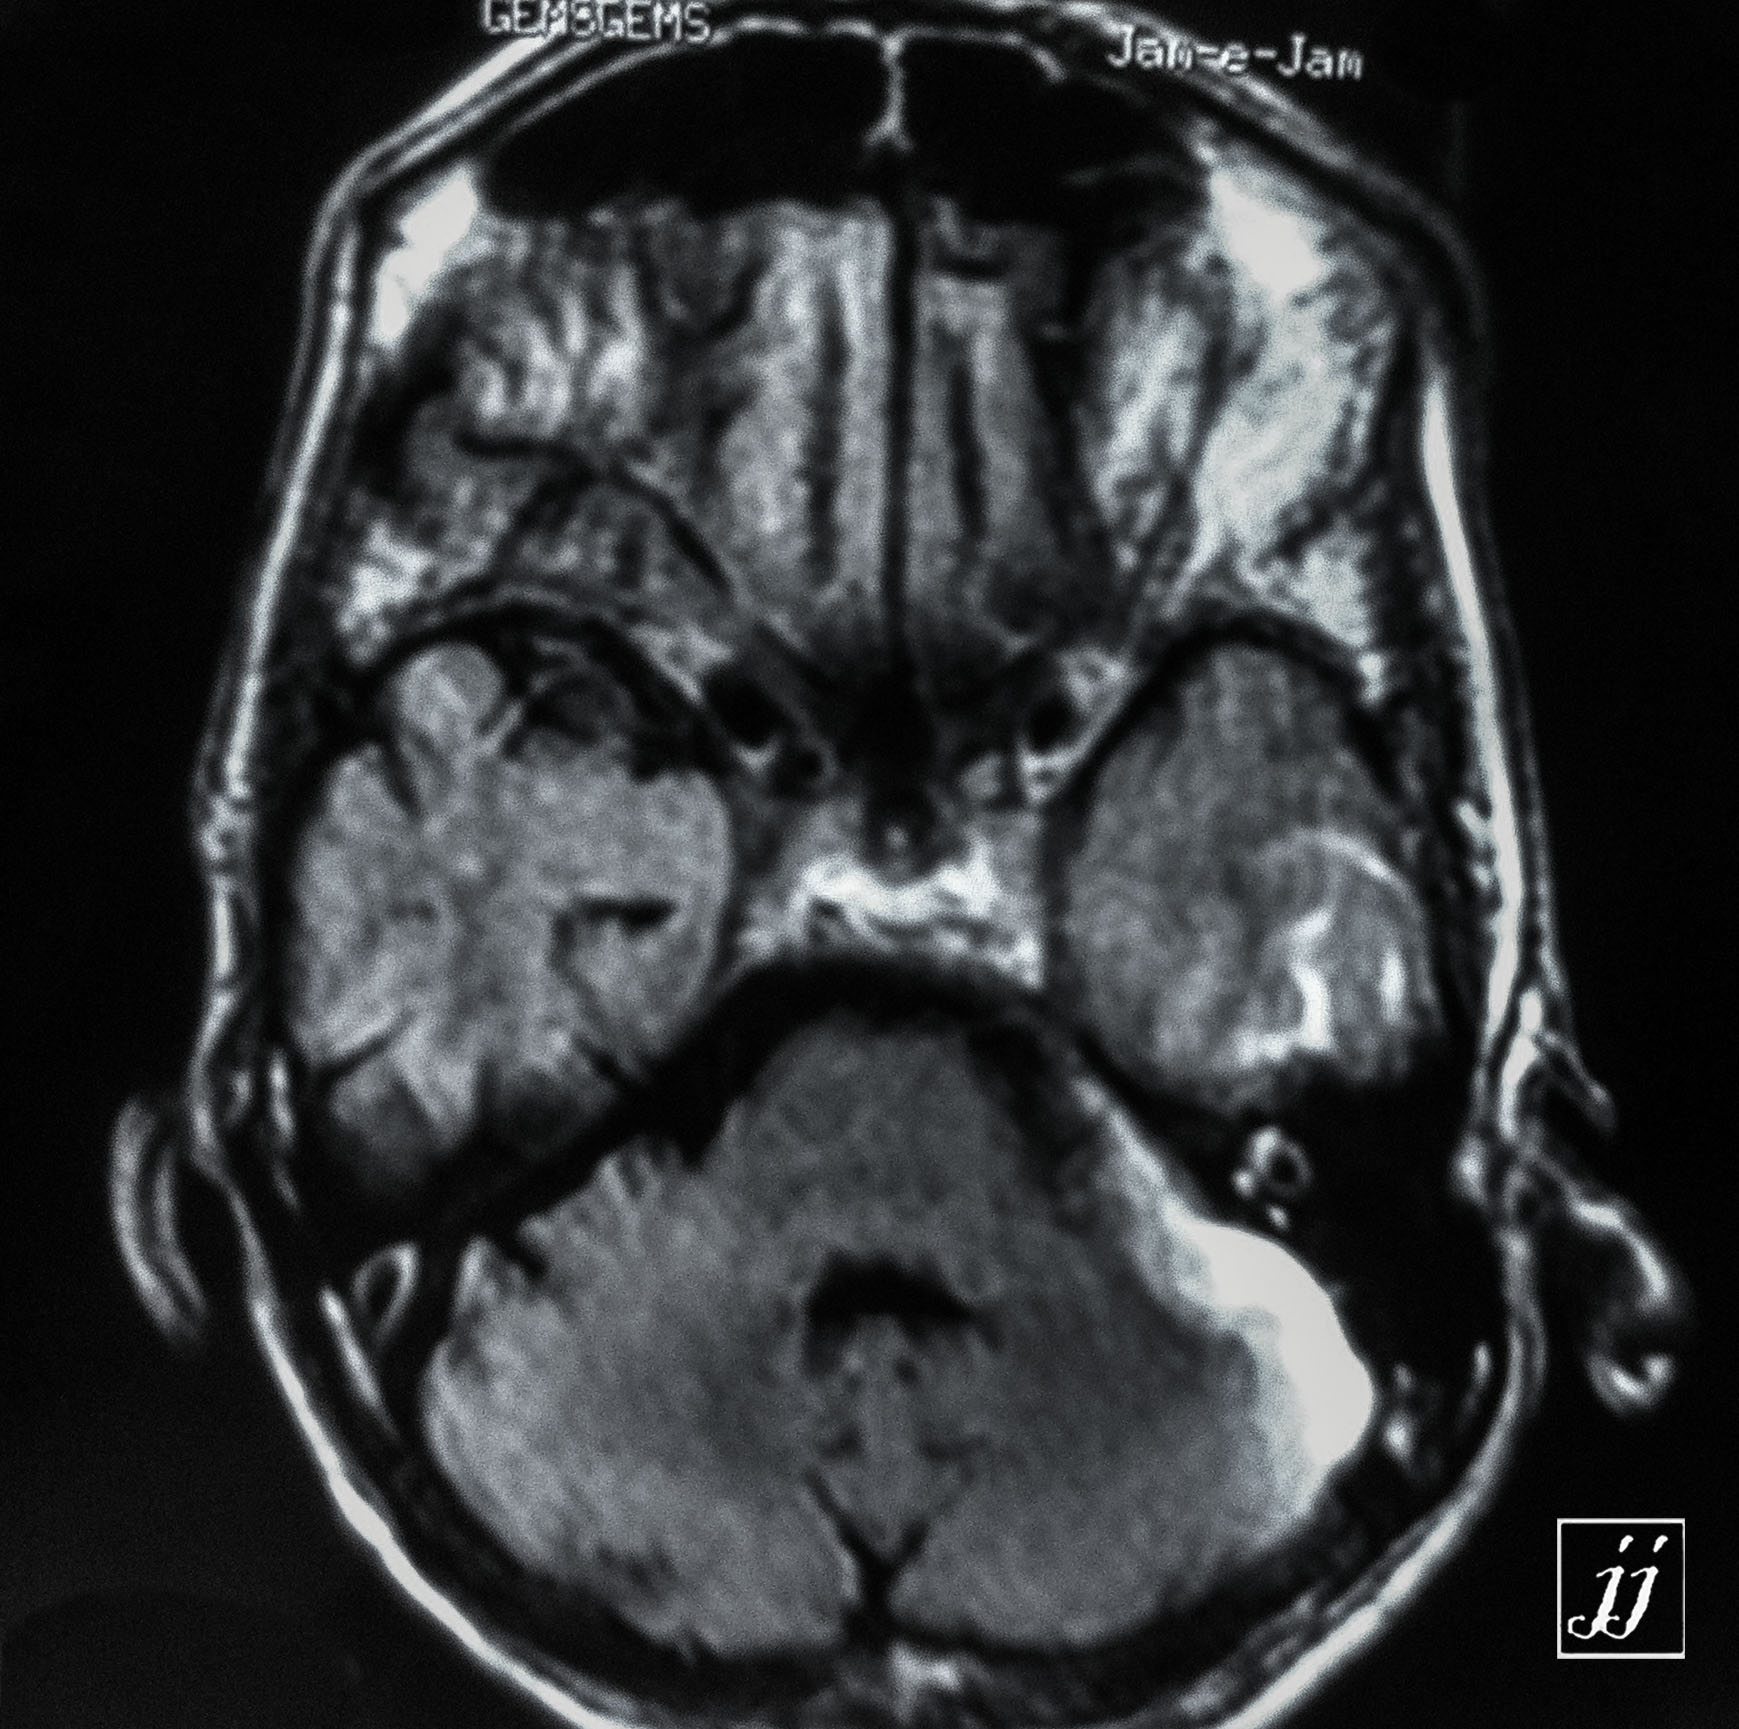

Brain- left side brain contusion edema and hemorrhage (4)